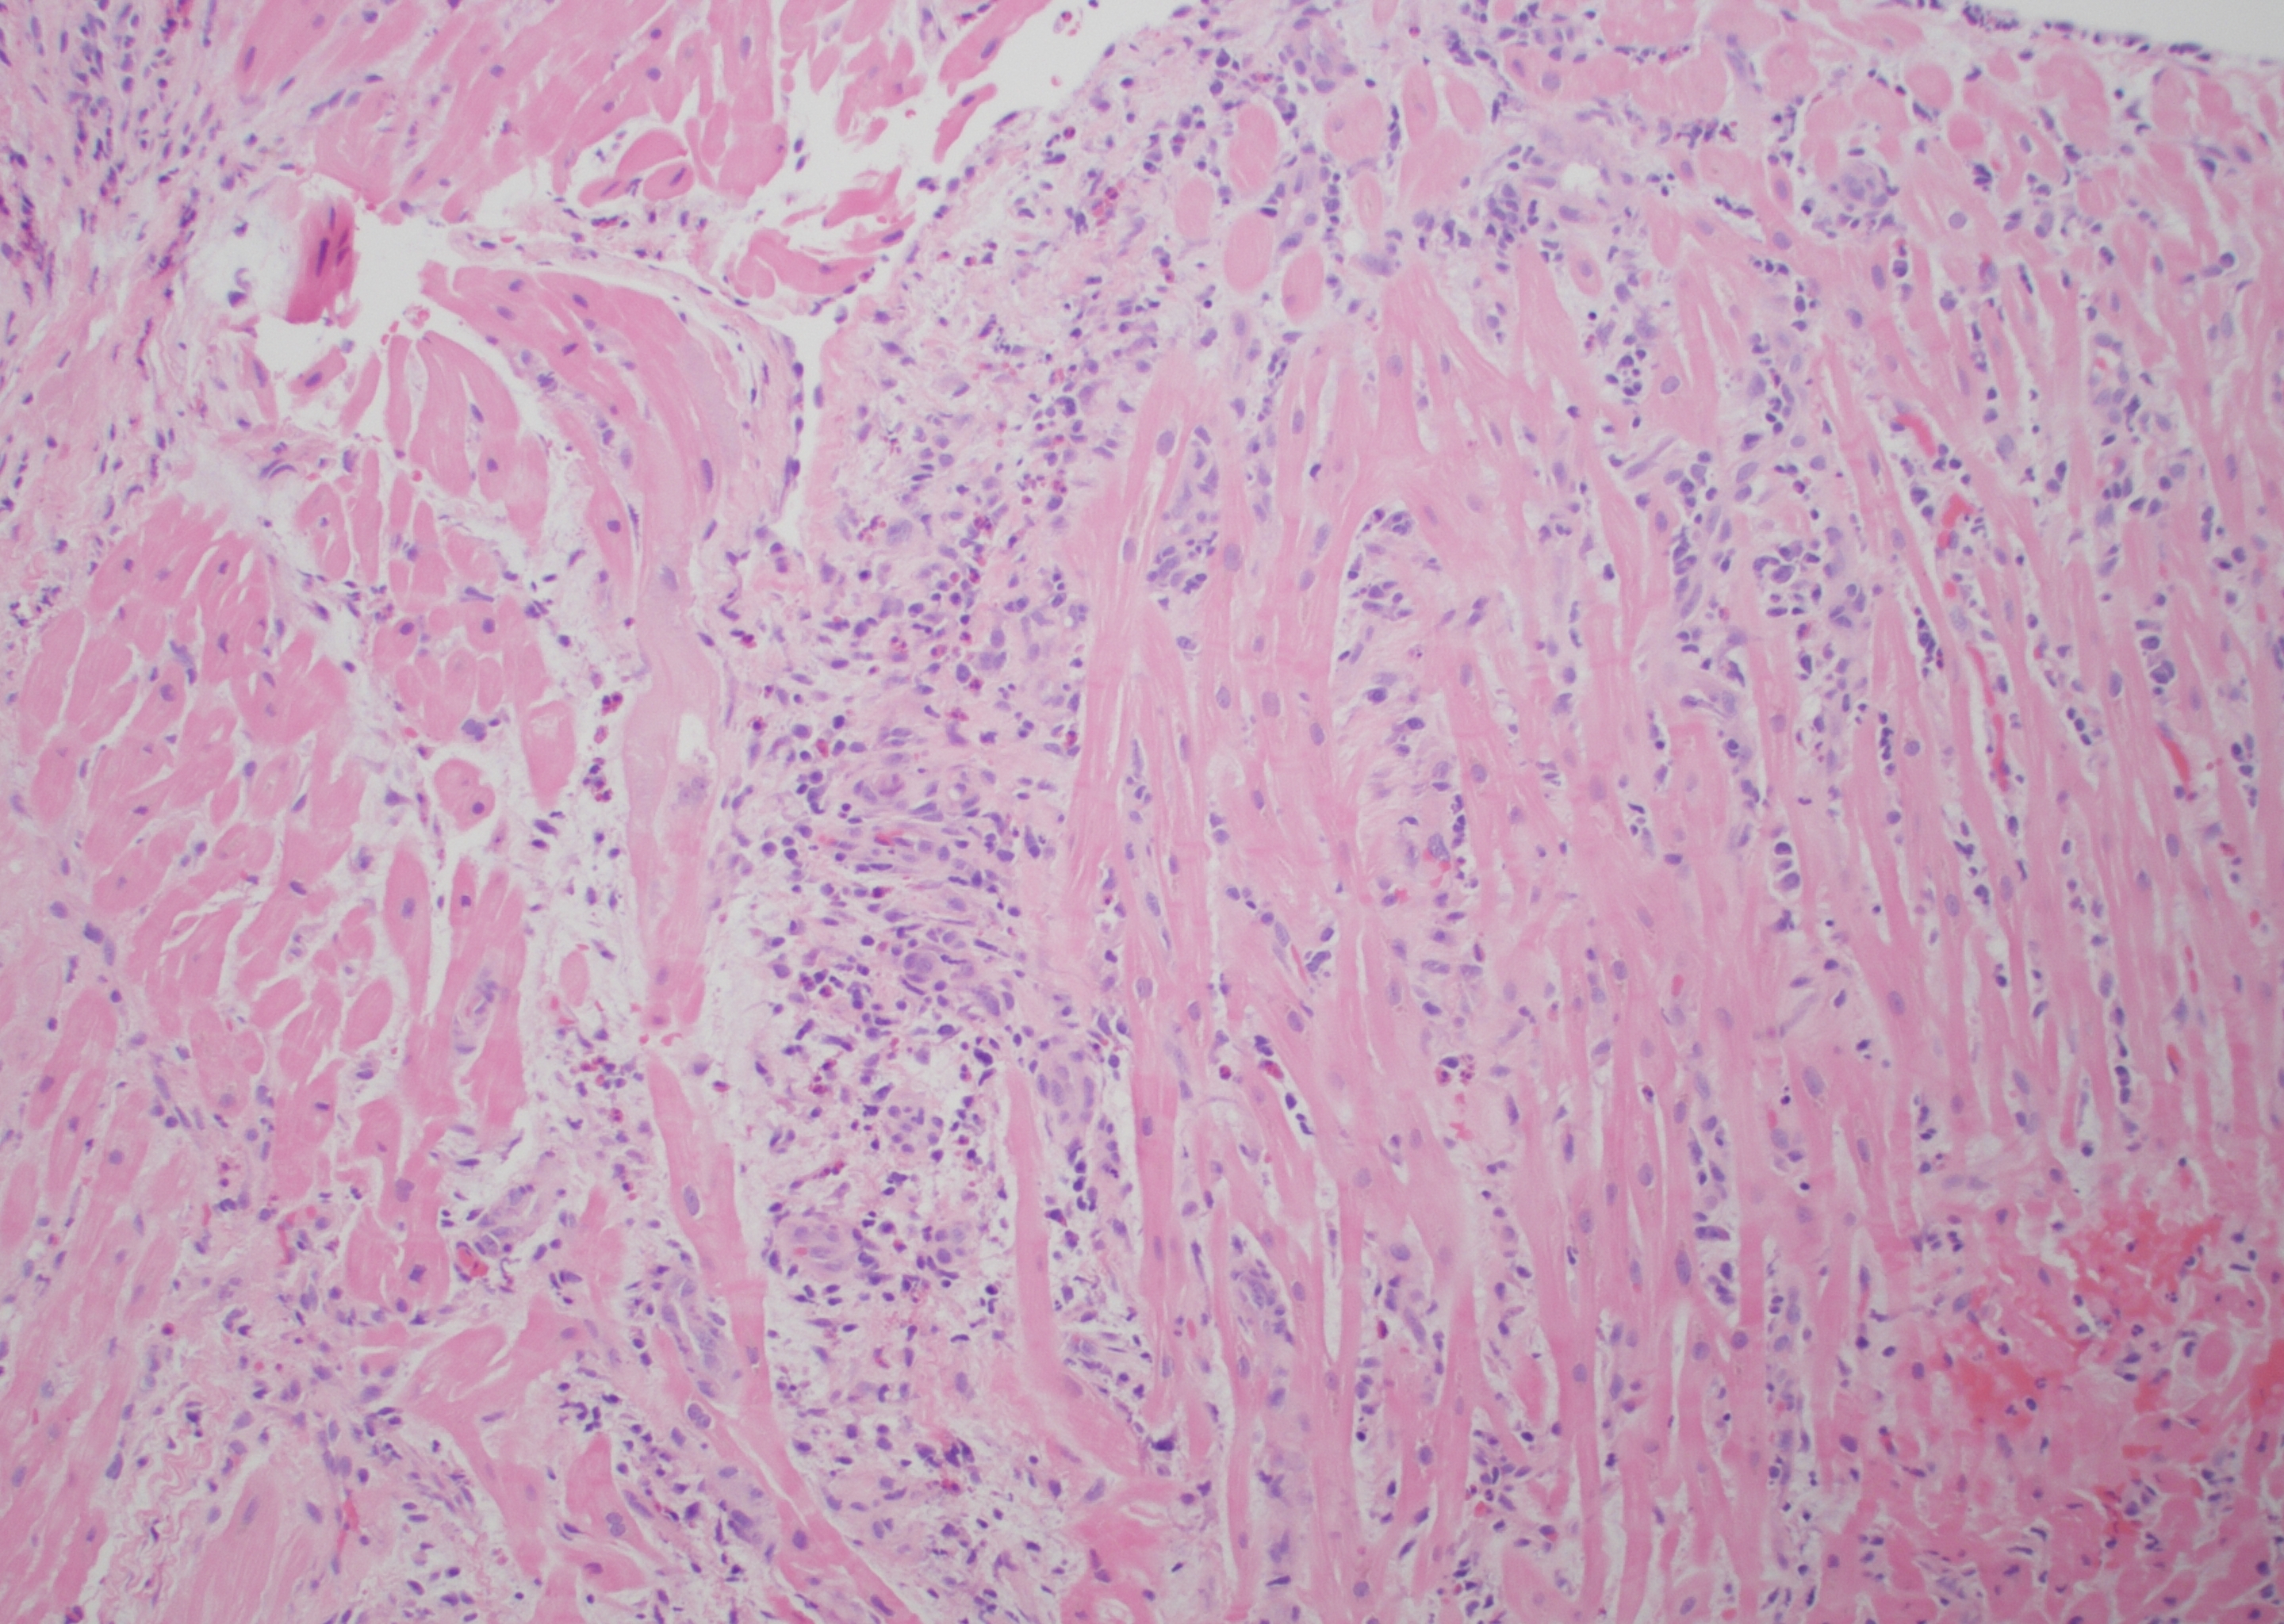

Abstract Body (Do not enter title and authors here): Eosinophilic myocarditis (EM) is a rare inflammatory myocarditis characterized by eosinophilic infiltration of myocardial tissue. Despite the high mortality rate, EM is frequently underdiagnosed and is often first identified in postmortem studies. We share a case of EM as an early manifestation of newly diagnosed eosinophilic granulomatosis polyangiitis (EGPA). The patient is a 46-year-old female with a past medical history of ulcerative colitis and adult-onset asthma who presented to the emergency department with a 2–3-week history of worsening positional chest pain radiating to the left upper extremity. Associated symptoms include 3 months of fatigue, headaches, right foot neuropathy, urticaria, and B-symptoms. Prior to admission, the patient was started on empiric prednisone for presumed EGPA. Initial lab work on admission was notable for elevated troponin (602 ng/L), hyper-eosinophilia (19.5%), thrombocytosis (680K/uL), and elevated ESR (42 mm/h) that have improved since initiation of prednisone. Transthoracic echocardiogram revealed a newly reduced LVEF of 40% with basal and mid-septal wall motion abnormalities. Cardiac catheterization showed normal coronaries confirming the diagnosis of non-ischemic cardiomyopathy. Late gadolinium enhancement in cardiac MRI was seen in basal to mid segments with patchy pericardial enhancement, meeting the Lake Louise criteria for myocarditis. An endomyocardial biopsy showed substantial myocardial infiltration with lymphocytes, histiocytes and eosinophils, confirming the diagnosis of EM. After multidisciplinary team discussion with cardiology and rheumatology, the patient was started on guideline-directed medical therapy for her HFrEF and pulse dose steroids with a prolonged taper and cyclophosphamide. She is tolerating her treatment well. This case highlights the importance of early recognition, comprehensive assessment and targeted treatment for EM depending on its underlying etiology. In the case of autoimmune dysfunction, it involves a combination of immunosuppressive and symptomatic therapy. Ongoing research is crucial to enhance our understanding and improve clinical outcomes, like arrhythmias and cardiogenic shock, for this complex condition.